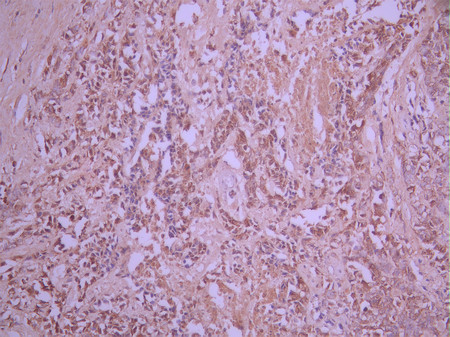

IHC image of CSB-RA805422A0HU diluted at 1:100 and staining in paraffin-embedded human brain tissue performed on a Leica BondTM system. After dewaxing and hydration, antigen retrieval was mediated by high pressure in a citrate buffer (pH 6.0). Section was blocked with 10% normal goat serum 30min at RT. Then primary antibody (1% BSA) was incubated at 4°C overnight. The primary is detected by a Goat anti-rabbit polymer IgG labeled by HRP and visualized using 0.05% DAB.

IHC image of CSB-RA805422A0HU diluted at 1:100 and staining in paraffin-embedded human breast cancer performed on a Leica BondTM system. After dewaxing and hydration, antigen retrieval was mediated by high pressure in a citrate buffer (pH 6.0). Section was blocked with 10% normal goat serum 30min at RT. Then primary antibody (1% BSA) was incubated at 4°C overnight. The primary is detected by a Goat anti-rabbit polymer IgG labeled by HRP and visualized using 0.05% DAB.